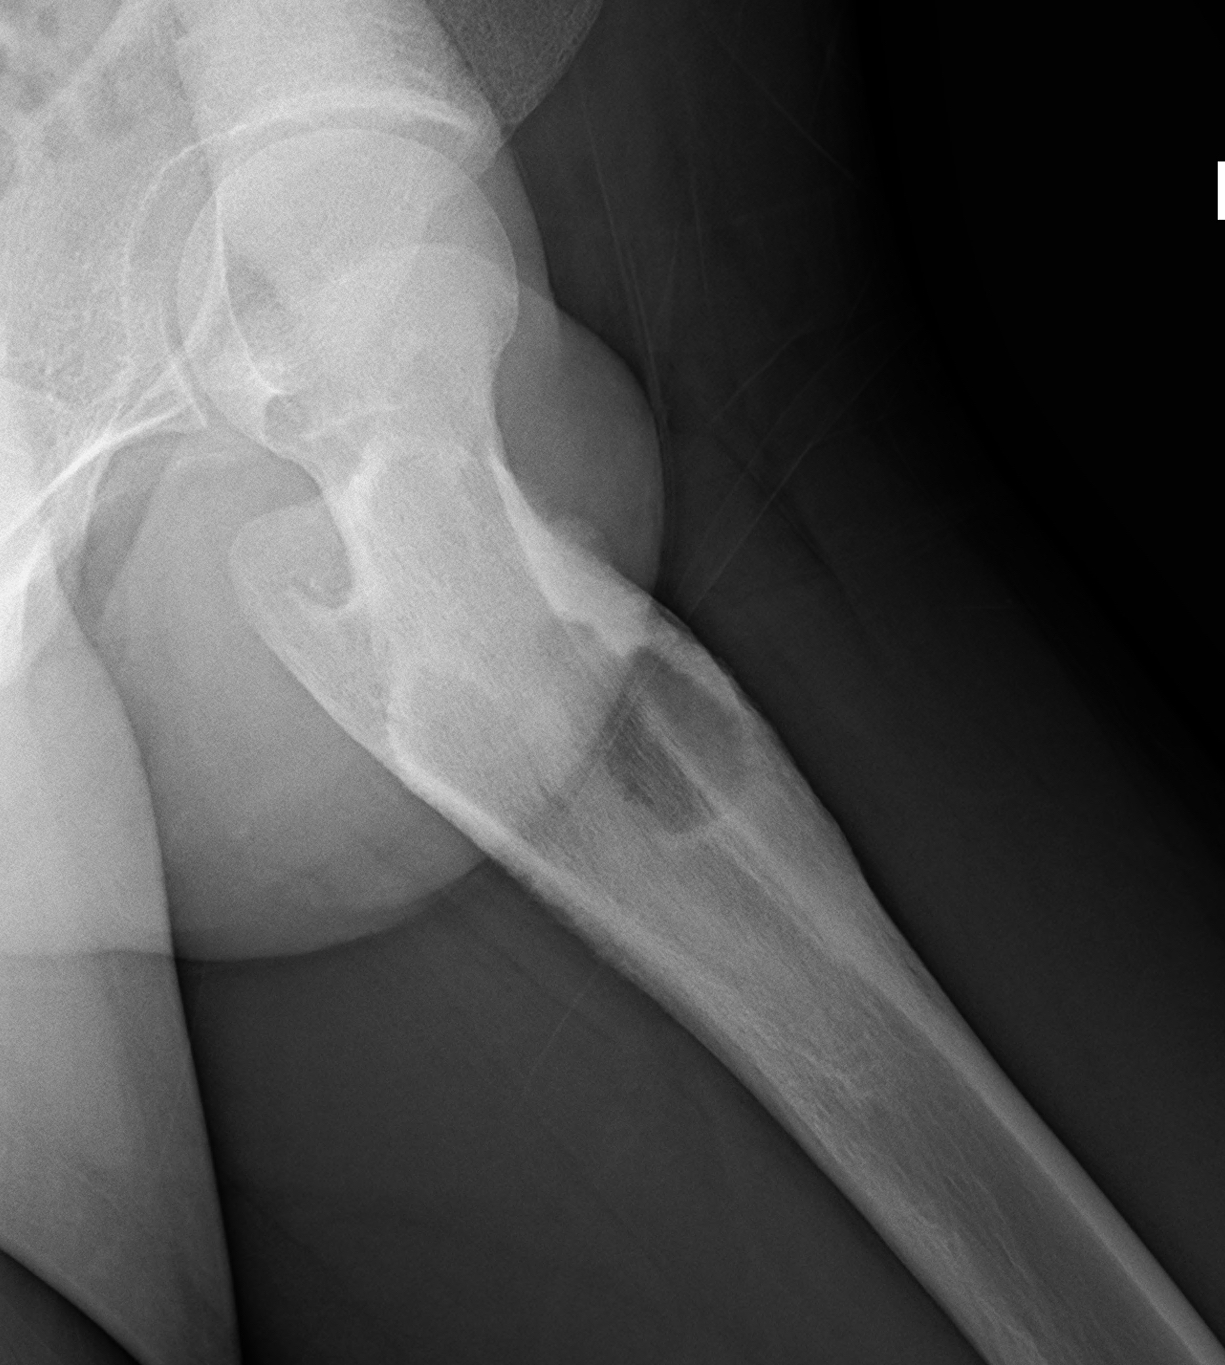

X-ray

Long bone

- more common meta-diaphyseal

- large faintly radiolucent lesion

- thin reactive rim

- may be expansile